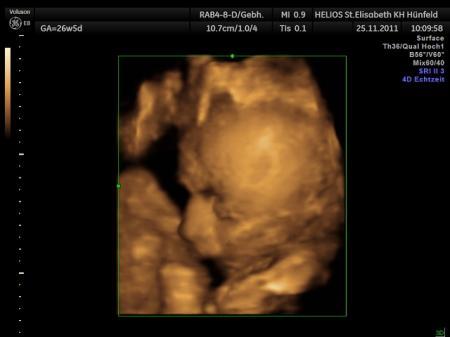

Bild zu Kindsbewegungen :-) - Forum für Februar - Mamis